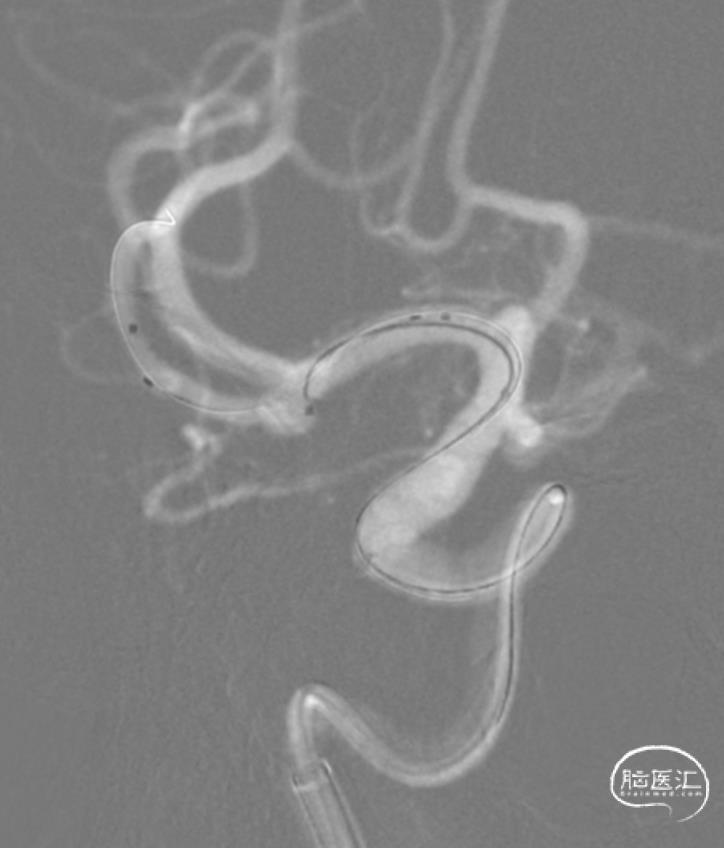

结束栓塞后,撤除Headway 17栓塞微导管,仔细观察,发现终末弹簧圈稍有脱出。

再三考虑,还是决定行Y支架。

置入第2枚支架。

Neuroform Atlas 3mm×15mm,充分保护瘤颈。

支架到位。

支架释放。